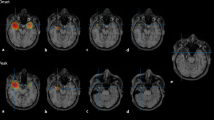

Patients with nonlesional neocortical epilepsy represent the most difficult group within the presurgical evaluation as only 35% are rendered seizure free following epilepsy surgery [27]. MEG can serve as a guide to identify very subtle lesions or to plan intracranial implantation in these cases (see later). If focal MEG clusters can be found they are definitely valuable in decision-making in these cases. In this difficult patient group, MEG was compared with other presurgical investigations and the intracranial gold standard. MEG lateralizes correctly in 86% of cases compared with 78% for ictal video-EEG monitoring (VEM), 70% for FDG-PET (fluorodeoxyglucose-positron emission tomography), and 57% for ictal SPECT (single photon emission computed tomography). MEG and ictal VEM identified the correct lobe in 65% of cases, FDG-PET in 57% of cases, and ictal SPECT in 52% of cases [10].

Besides the important role of MEG in nonlesional cases, it is also of important value in lesional cases. Focal cortical dysplasia (FCD), for example, is a highly and intrinsically epileptogenic lesion often causing intractable epilepsy treatable with epilepsy surgery. MRI can identify these lesions by showing blurring of the gray–white matter, cortical thickening, and abnormal signs in the white matter; however, the lesions might also be very subtle or even microscopic and not visible on optimal imaging. Owing to their intrinsic epileptogenicity, MEG plays an important role in the delineation of their extent and in predicting the outcome following resection [31]. Itabashi and colleagues concluded in their study on patients with very subtle and initially overlooked FCD that MEG-guided a posteriori review of MRI should become clinical practice [8].

Only a few are reported here: Stefan et al. performed a retrospective study including 455 cases and concluded that MEG identified the correct lobe in 89% of cases and added information in 33% and crucial information in 10% [23]. Knowlton et al. reported on a positive predictive value (PPV) of MSI for seizure localization of 82–90% depending on whether it was computed against intracranial recording alone or in combination with surgical outcome [13]. Knowlton et al. showed that a highly localized MSI result was significantly associated with seizure-free outcome [14]. Based on a retrospective analysis of the value of MEG performed at Cleveland between 2009 and 2012, Vadera et al. found that when preoperative MEG studies were fused with postoperative MRI, for 30 of 65 patients the MEG cluster was located within the resection cavity, for 28 of 65 completely outside the cavity, and for seven of 65 partially within; they showed a significantly improved likelihood of seizure freedom with complete clusterectomy in patients with localization outside the temporal lobe [30]. Englot et al. reported on 132 surgical cases. They concluded that a concordant and specific MEG result predicted seizure freedom with an odds ratio (OR) of 5.11 [5].

Various studies evaluated how the inclusion of MEG in the decision-making process changed patient management (Table 1). Overall, the studies concluded that adding MEG to the presurgical protocol changes management in 1/5–1/3 patients (depending on the inclusion level; [9, 14, 25, 29]).